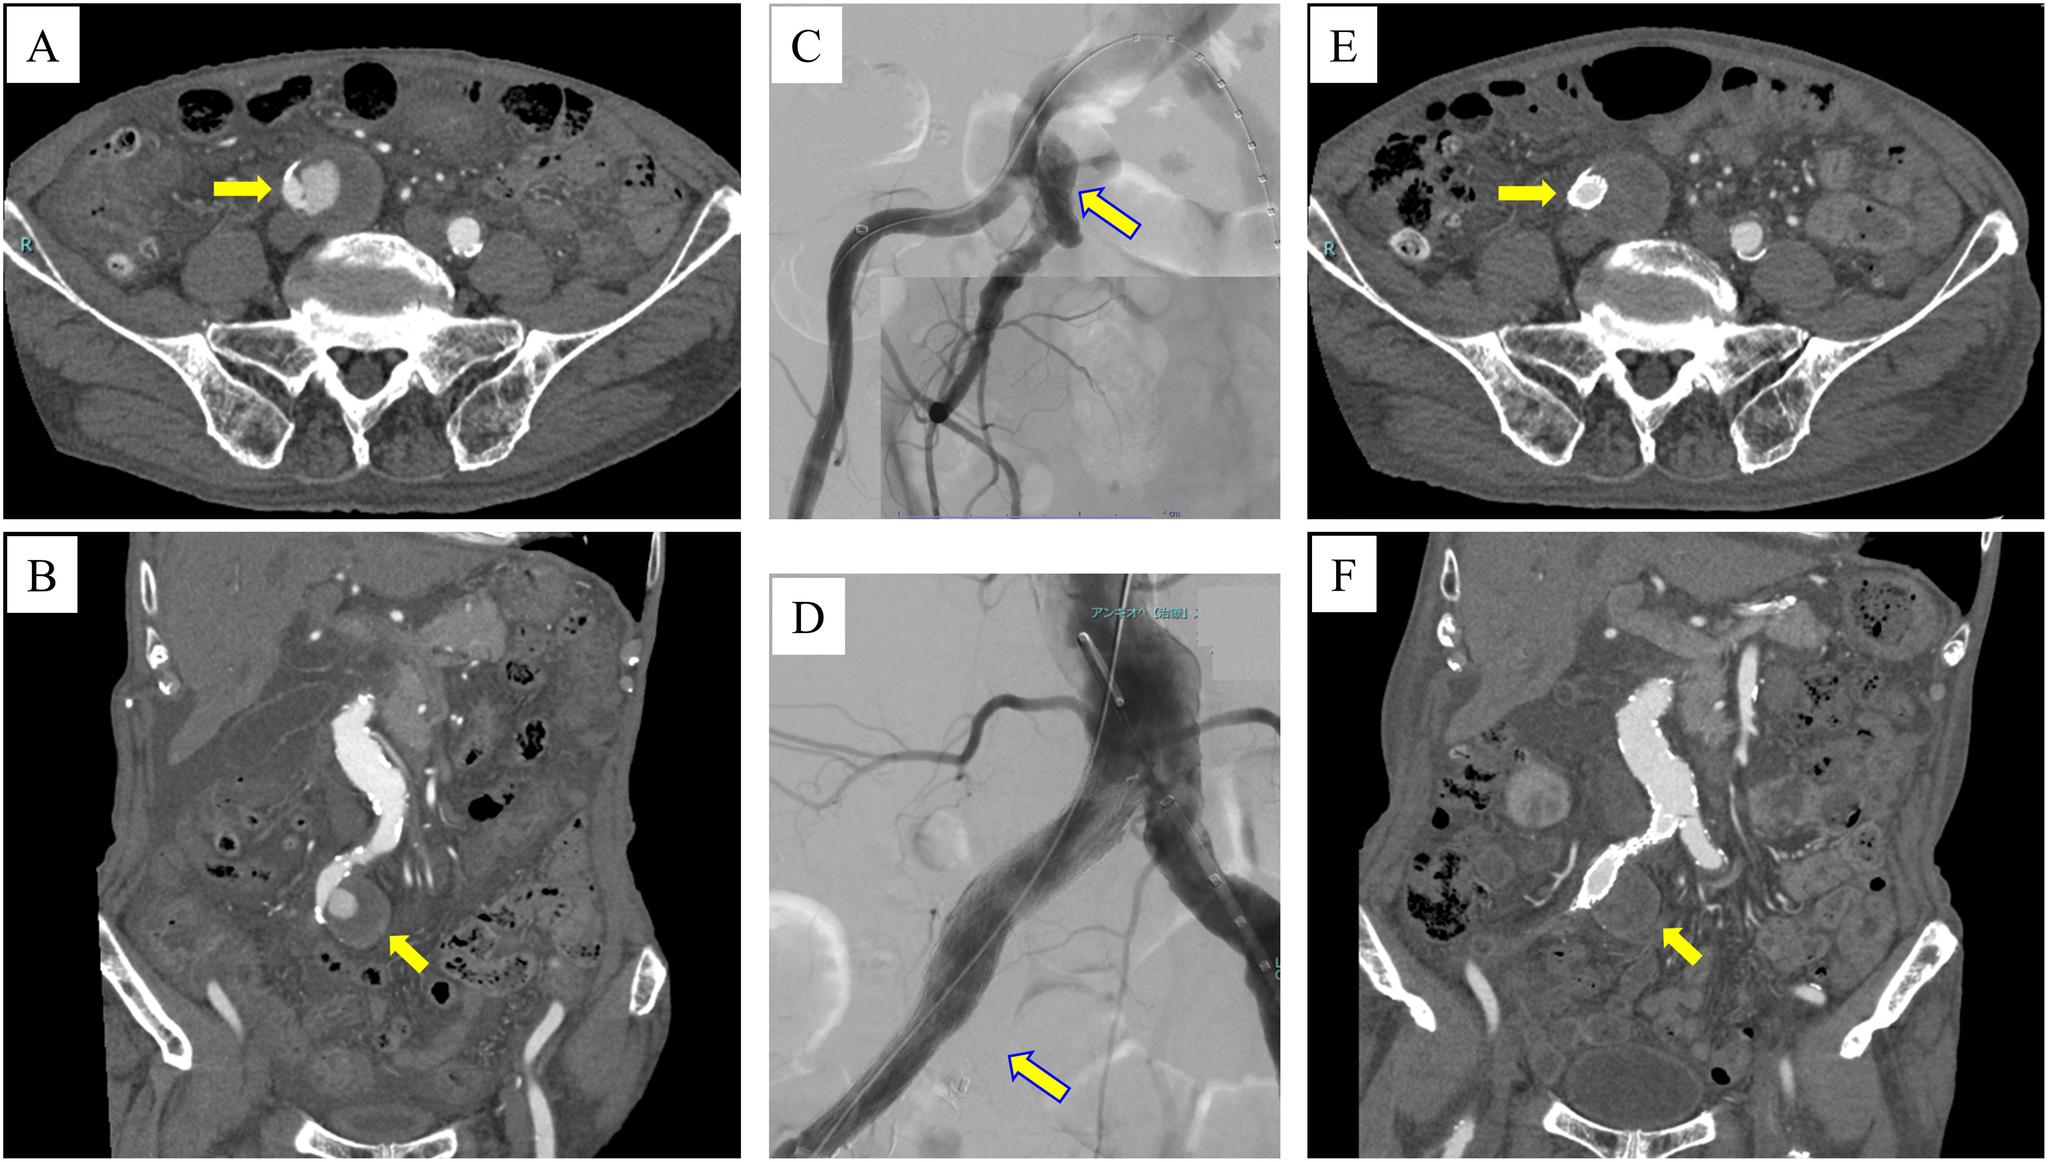

We report a case of an 83-year-old man with a ruptured internal iliac artery (IIA) aneurysm after endovascular repair, which was treated via the ligation of IIA and tight suture of the aneurysm sac. Although there were no findings of obvious endoleak after endovascular treatment, the IIA aneurysm increased in size and eventually ruptured. We presumed that pressure to IIA aneurysm via the embolized IIA led to rupture. Aneurysm sac expansion may lead to a rupture despite no endoleak being detected; therefore, close follow-up or re-intervention must be considered. Tight embolization of IIA may prevent endotension in the same case.